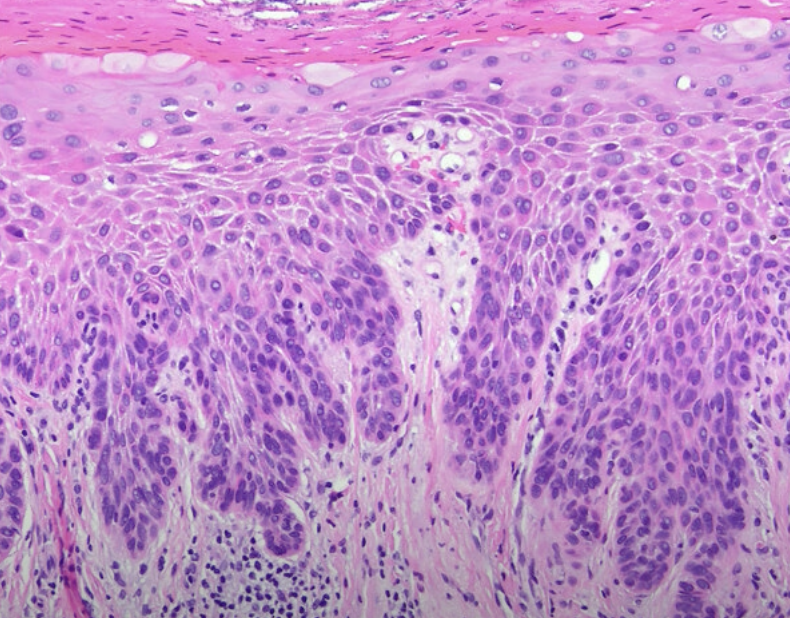

Oral epithelial dysplasia (OED)

- 分為三個程度

Moderate

- 到中三分之一

Sever